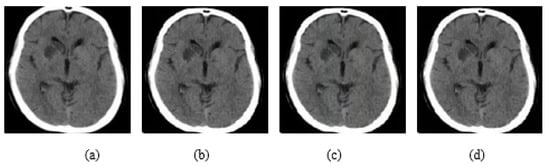

In addition, experiments were performed with FGSM, PGD, and Square Attack for ϵ values equal to 0.01, 0.03, 0.05, 0.07, 0.09, 0.12, and 0.15. In Figure 6, MRI with aforementioned attacks and ϵ = 0.01 are presented. The human eye cannot understand any difference between these images. In Figure 7, attacks with ϵ = 0.07 are depicted. Square Attack causes the biggest distortion compared to FGSM and PGD. However, small changes can be observed also in the other two attacks. In Figure 8, the ϵ value has been increased to 0.15, making the noise perceptible.

Figure 6.

(a) Initial Image, (b) FGSM attack with ϵ = 0.01, (c) PGD attack with ϵ = 0.01, (d) Square Attack with ϵ = 0.01.